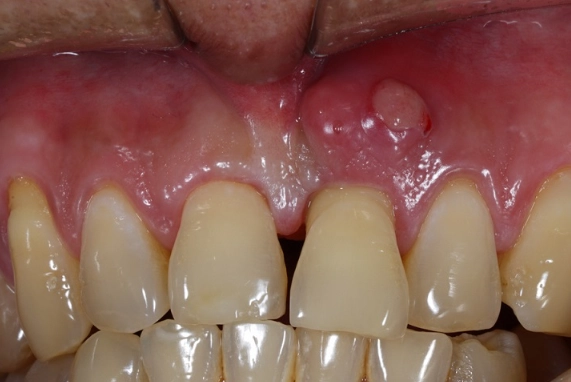

The specific code is K04.7 - Periapical abscess with sinus. Now, the 'with sinus' part confuses everyone at first. In dental terms, a 'sinus' here doesn't refer to your nasal sinuses. It means a sinus tract – a small, channel-like opening that the abscess creates to drain pus, often appearing on the gum as a pimple-like bump called a 'parulis' or 'gum boil.' This is the body's attempt to relieve pressure.

Then comes the clinical exam. They'll visually check the tooth and gums, looking for cavities, large fillings, cracks, or that tell-tale gum boil (sinus tract). They'll gently tap (percuss) on several teeth. The infected one will often feel exquisitely tender to this tapping. They might use a cold test (a quick shot of cold air or a cotton pellet with a freezing agent) on the tooth. A dead tooth won't feel the cold at all, while a dying one might have a prolonged, painful response.